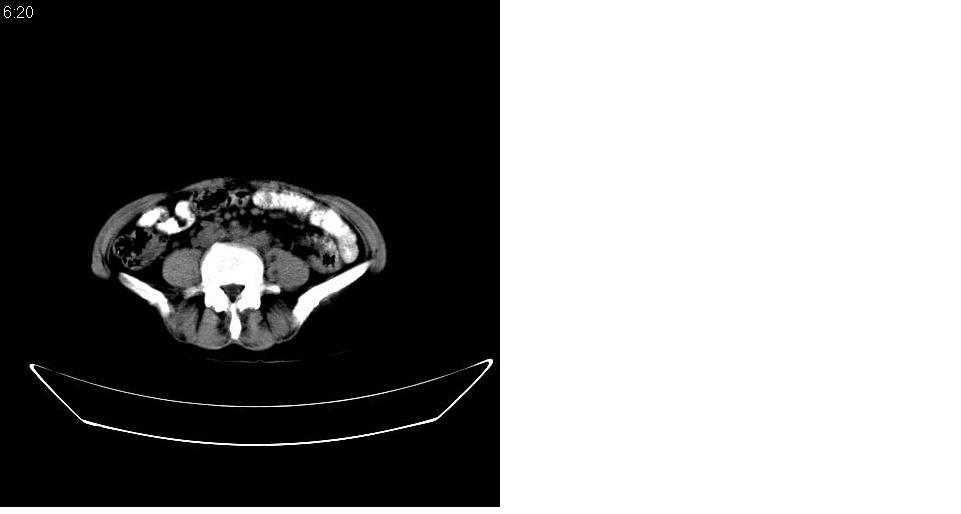

女 53岁,大便每天四到五次,变细,伴有粘液,病人家属说,去年五月在外院行子宫肌瘤术。

腹膜后多发肿大淋巴结肿大并融合改变;右侧回盲部可见团块样软组织影,不规则;

腹膜后诸多淋巴结,右侧髂窝软组织块影,综合患者大便次数、形状改变,考虑结肠回盲部肿瘤